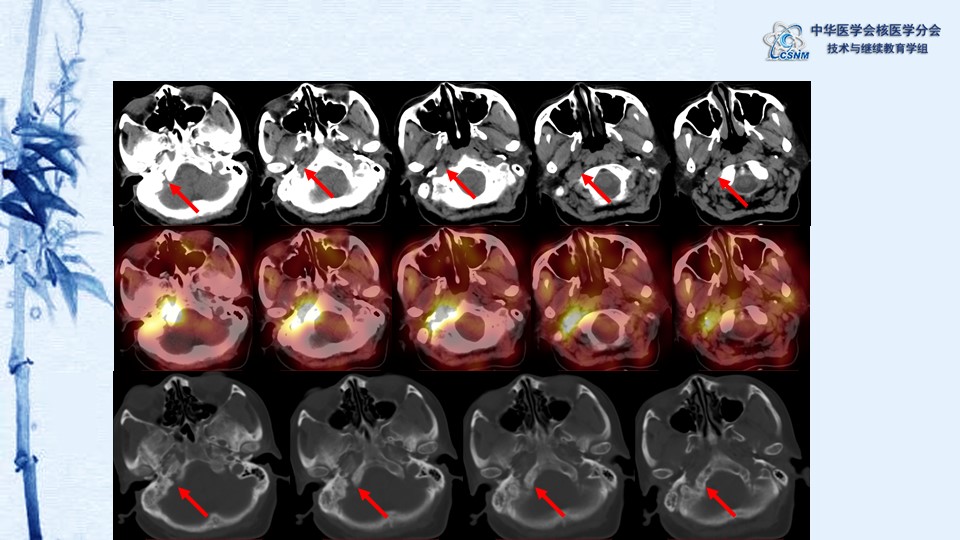

病例88:顱底占位生長抑素受體顯像一例-胡桂蘭